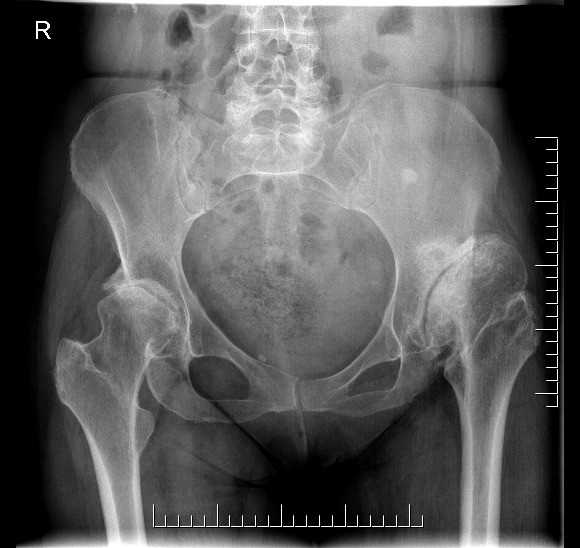

Cerebral Palsy

Issues

- spasticity / joint contractures

- hip subluxation /dislocation preoperatively

- dysplastic femoral head / acetabulum

Results

O'Driscoll et al Arthroplasty Today 2022

- systematic review of 7 studies and 189 patients

- mild and severe CP

- mean 8 years follow up

- dislocation 11%, aseptic loosening 6%, infection 3%, fractures 3%